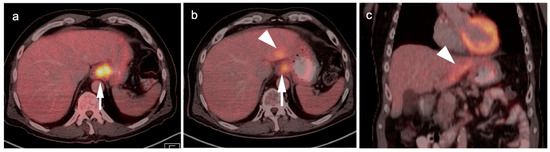

5. Cholangiocarcinoma